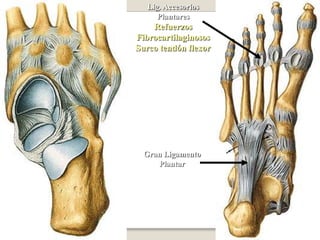

ARTICULACIONES METACARPOFALINGICAS E INTERFALINGICASLa cinta transversal une la cabeza de los 4 últimos metacarpianos (2º al 5º), por delante de las articulaciones  metacarpofalángica.

ARTICULACIONES CARPOMETACARPIANAS E INTERMETACARPIANAS

ARTICULACIONES INTERCARPIANAS

Articulación mediocarpiana

Ligamentos mediocarpianos palmar y dorsalposterioranterior